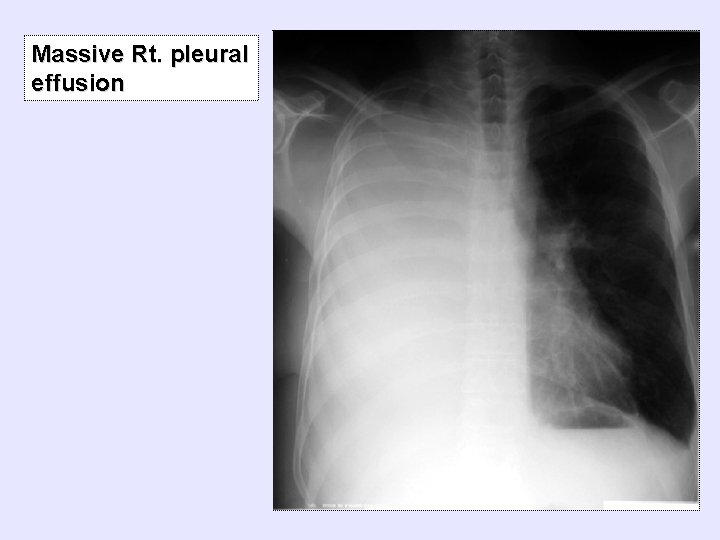

Massive Rt. pleural effusion